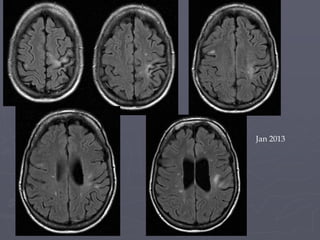

MRI Scan pre treatment,

T2, postcontrast

Jan 2011

T2

postcontrast

2011 - 2014

• Stable on Tysabri